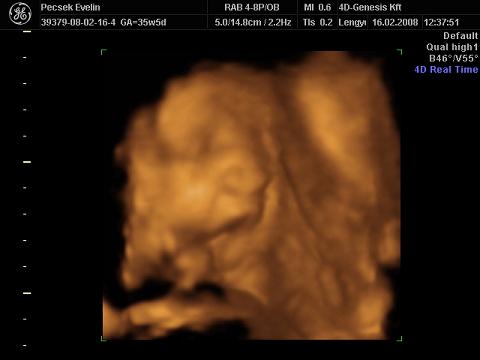

Voltunk 4D-s UH-n is, igaz, hogy 02.16-án (33. héten), de most teszek fel képeket és adatokat a gép hibája miatt

súly: 2211g

BPD: 8,35cm

OFD: 10,62cm

HC:30,3cm (nekem születéskor volt 30cm a fejkörfogatom :shock: )

AC:29,67cm

FL:6,45cm

Liza nőiessége:

ásít, már nagyon únja a banánt :lol: :

itt a nyelvét nyújtogatja:

kezével csikizi a saját kis talpát :lol: :

Liza megmutatta az arcát a végére (egész végig takarta a kezével és lábával, bezzeg a punciját azt nem):

Viszont mindenki azt mondja a környezetembe (a családba is és ha vásárolni megyek akkor az eladók is), hogy nagyon lent van a hasam. A 4D Genesis-es nőci is azt mondta miközben csinálta az UH-t, hogy nagyon lent van a lepény és a baba feje is, a lepény 2-es fokban érett :shock: :shock: Lehet, hogy hülye kérdés, de ez most mit jelent?